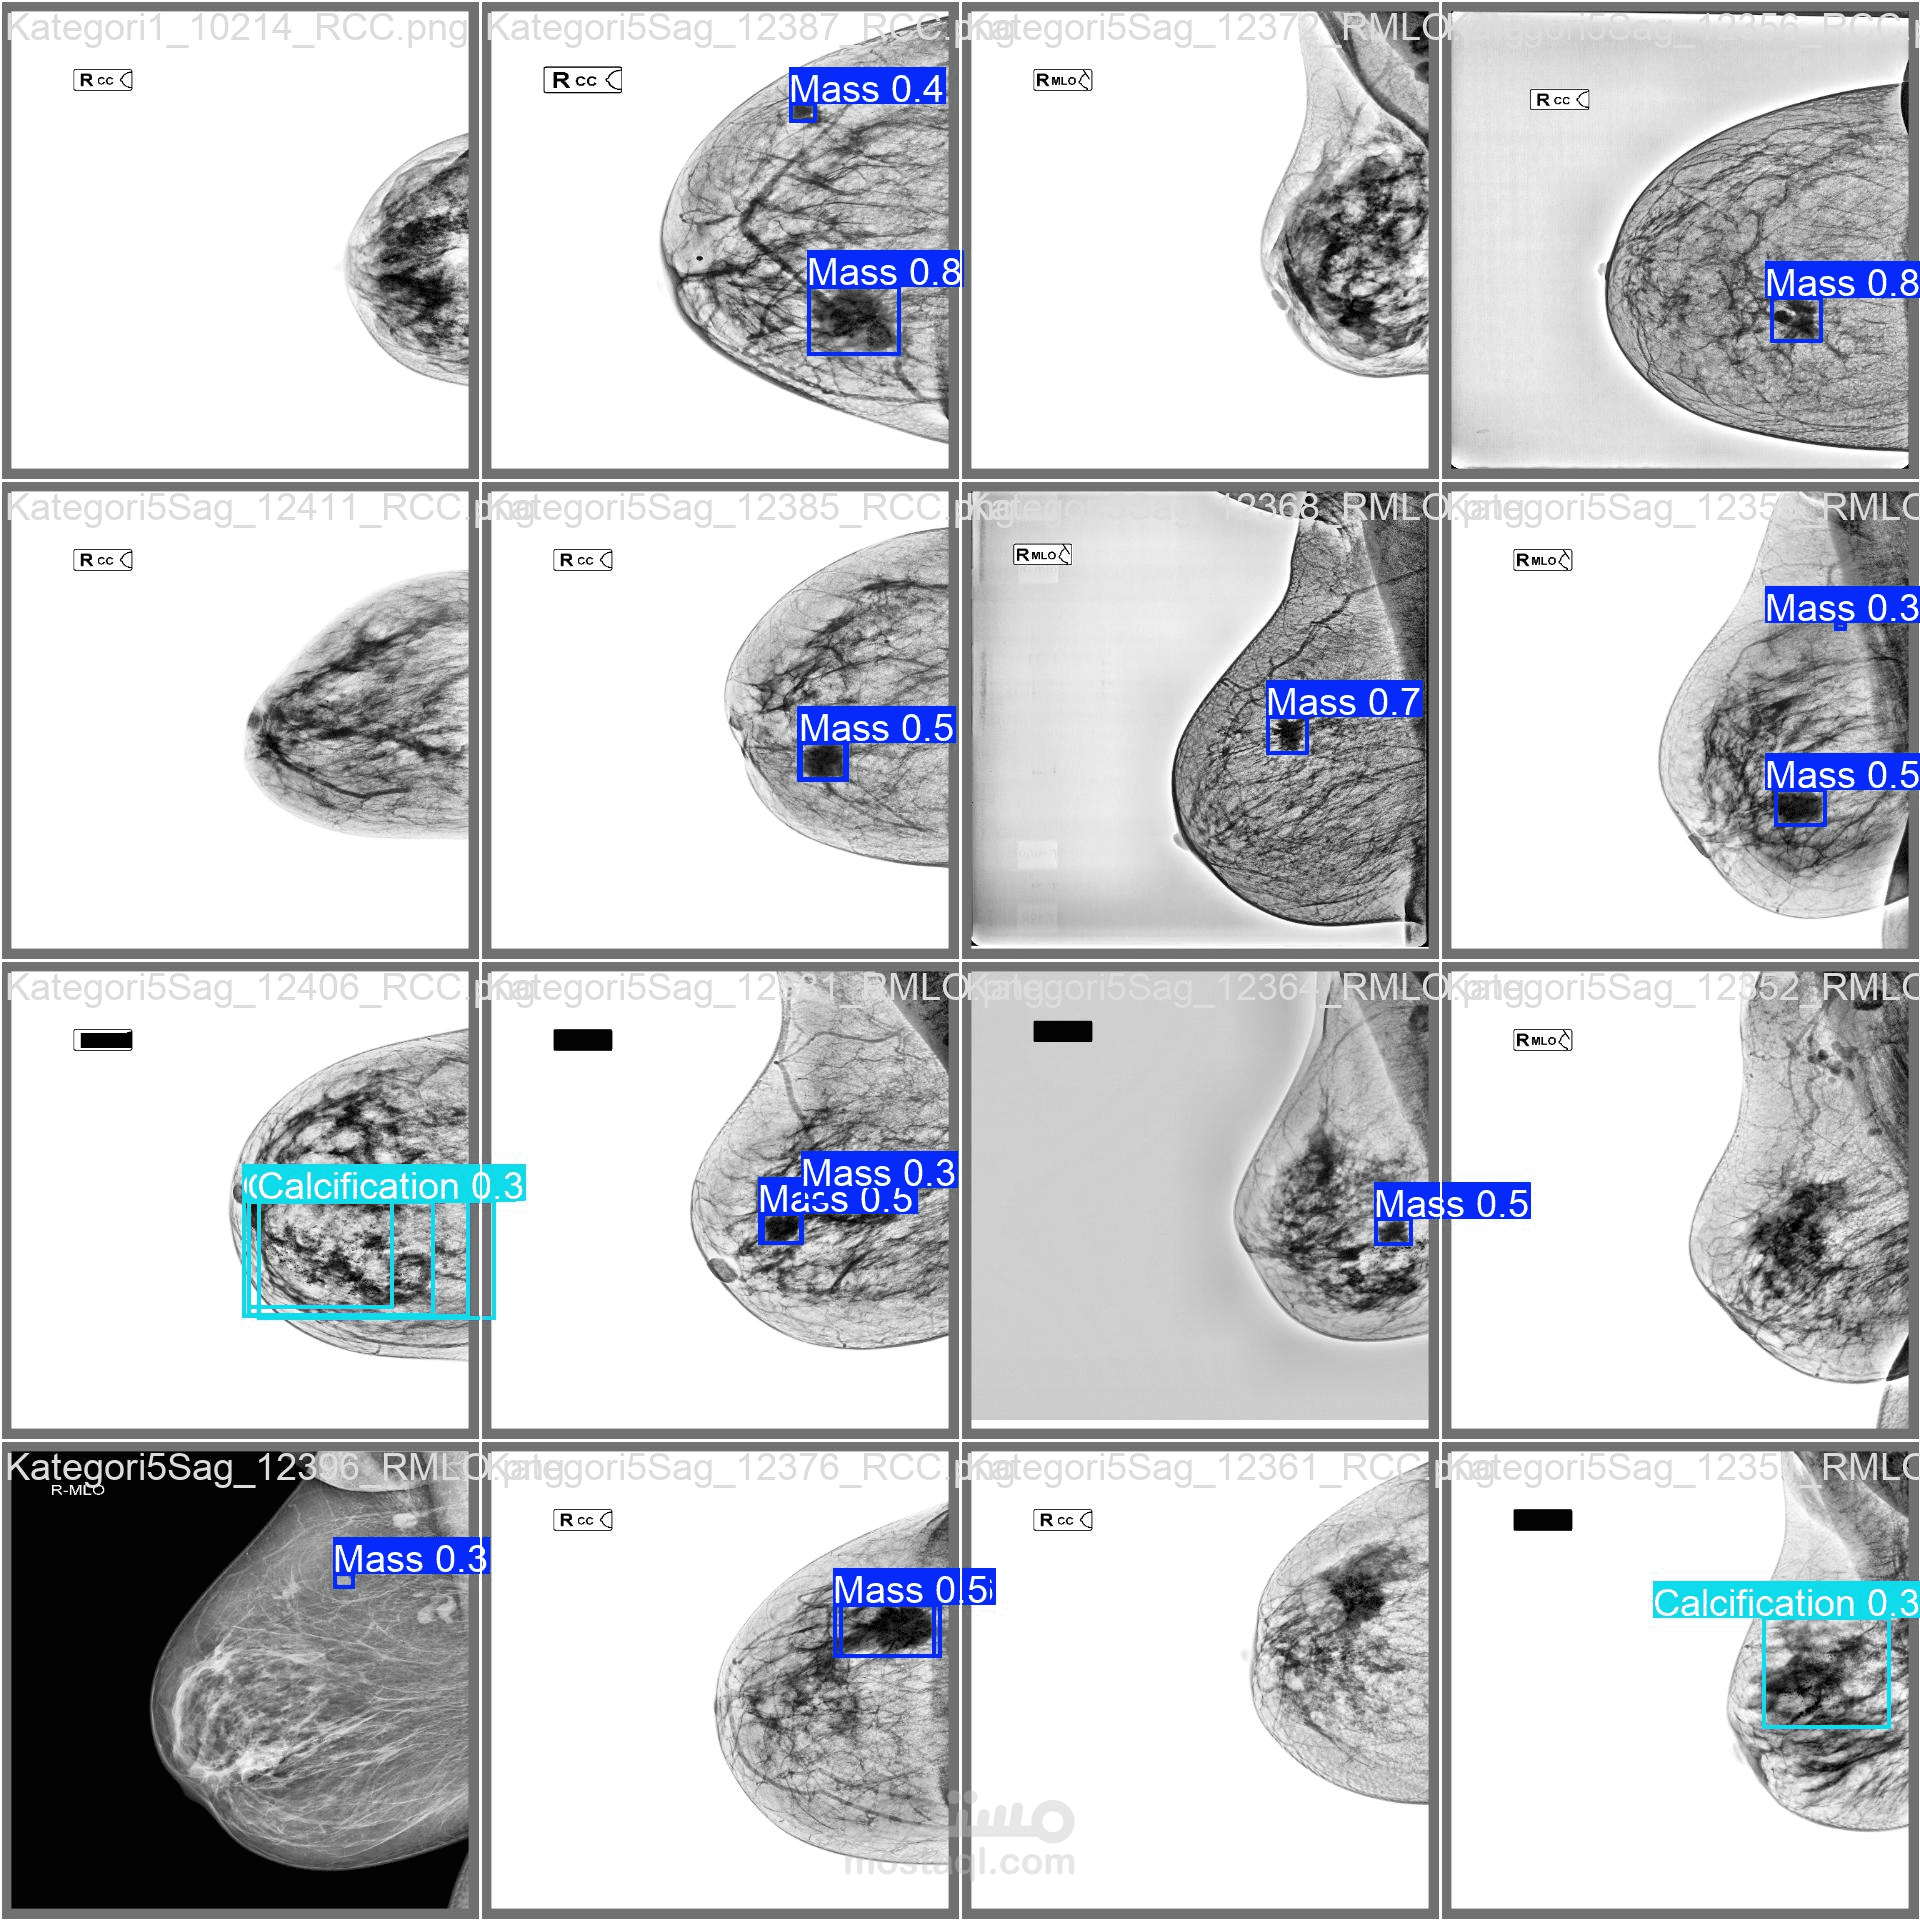

قمت بقيادة فريق "Pixelers" في مسابقة الذكاء الاصطناعي في الصحة ، وحققنا المركز الثالث عشر من بين 5,393 فريقًا مشاركاً. ركز مشروعنا على تطوير نماذج الذكاء الاصطناعي لاكتشاف الآفات في صور الماموغرام، وتصنيف أنواع BIRADS، واستخدام معالجة اللغة الطبيعية (NLP) لتحليل التقارير الطبية. كنت مسؤولاً عن قيادة الفريق، ومعالجة البيانات، وتطوير النماذج باستخدام YOLOv10 لاكتشاف الكتلة والكلس الموجودين في صور الأشعة السينية للثدي و استخدمت نموذج ال U-Net للتقسيم. نجحت في إدارة دمج نماذج التعلم الآلي من مرحلة إعداد البيانات حتى النتائج النهائية، مما ضمن دقة عالية في اكتشاف الكتلة والكلس, وكفاءة في تنفيذ المشروع.